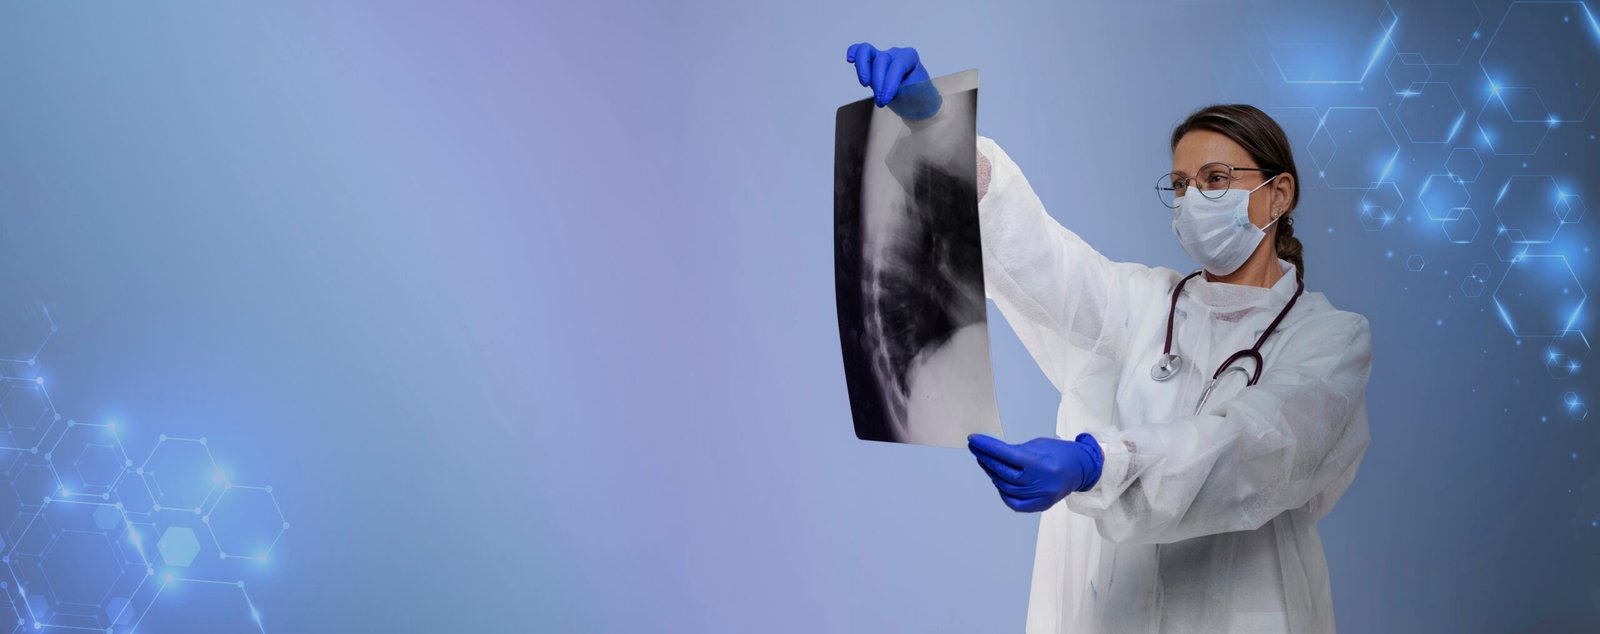

Atención de enfermedades agudas y crónicas

Diagnóstico y manejo integral para control y prevención de enfermedades respiratorias en Mérida, Yucatán.